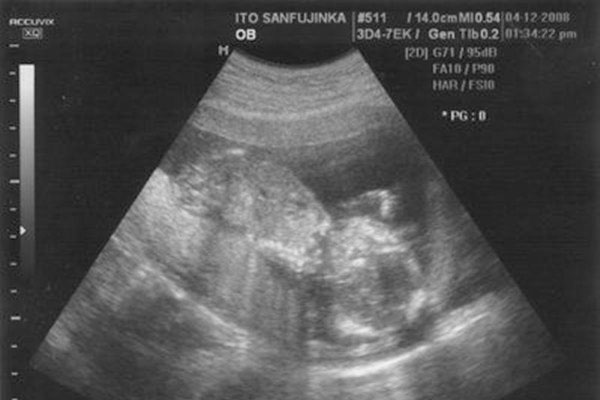

怀孕40天孕囊大小看男女

1、b超数据看胎儿性别,如果长和宽的相差在一倍以上男宝宝可能性大。

2、孕囊早期数据,长和宽相等,女宝宝可能性大。

3、怀孕40天时,孕囊形状上像茄子或长条状,男宝宝可能性大。

4、怀孕40天时,孕囊形状圆圆的,女宝宝可能性大。

5、孕早期,7W+1D的b超数据,胎囊2.91.9,生的是男孩。

6、60天的b超数据,孕囊大小是3.61.6MM,生下的是男孩。

7、46天b超数据,孕囊数据201717,是女孩。

8、怀孕8周,孕囊数据是1.61.7,生下的是女孩。